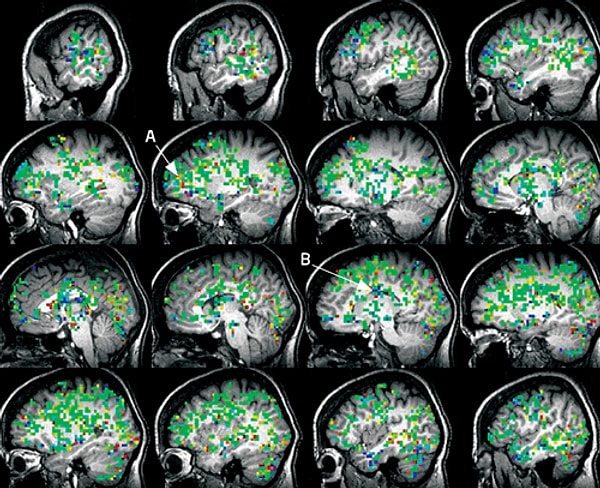

Именно эти нервы и вызывают мощный выброс гормонов, влиявших на овуляцию у далеких предков наших дам. Причем находится центр гормонального скачка в головном мозгу, и к работе привлекаются почти все его области, не только те, что отвечают за работу внутренних желез. Поэтому оргазм и ощущается женщиной всем телом! Возбуждение клиторальных нервов в буквальном смысле пробуждает всю нервную систему.